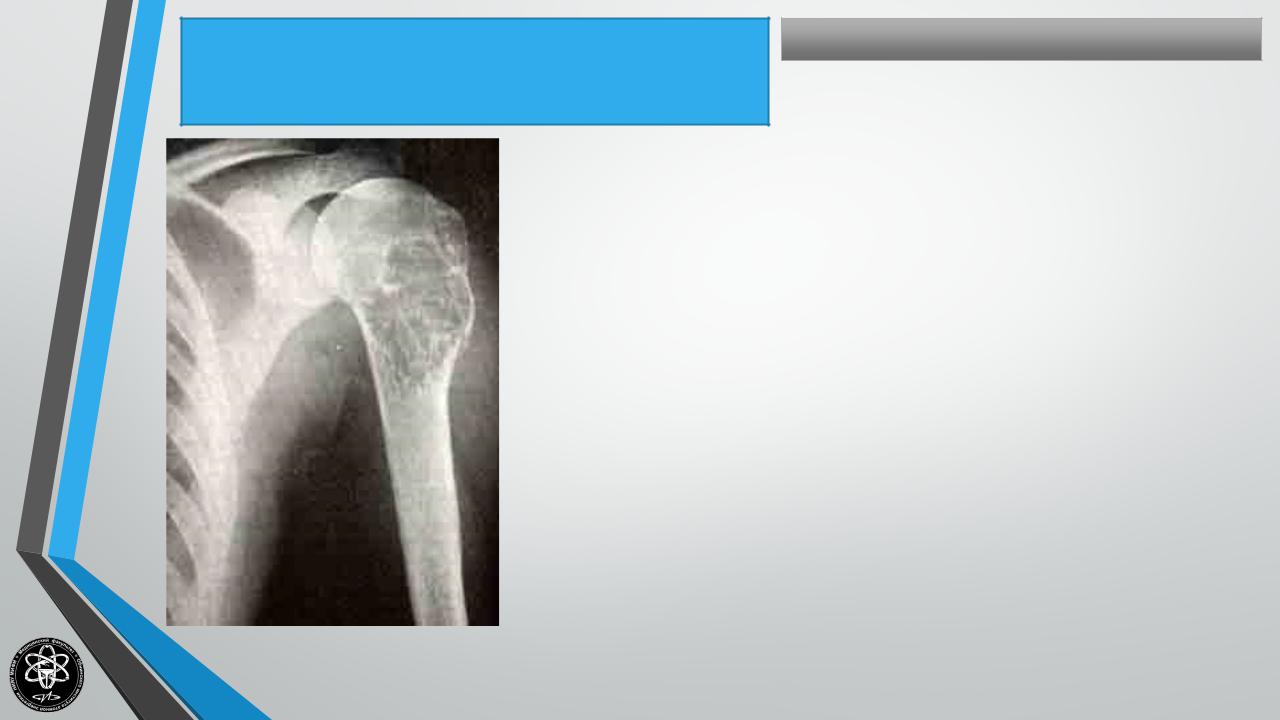

ОСТЕОБЛАСТОКЛАСТОМА(КОСТНАЯКИСТА, Частные вопросы костной онкологии

ГИГАНТОКЛЕТОЧНАЯОПУХОЛЬ, АНЕВРИЗМАКОСТИ)

Частота — 7,6% опухолей скелета. Поражаемый возраст — 10 — 40 лет.

Частота у мужчин и женщин примерно одинаковая. Формы: литическая и ячеистая.

Течение прогрессирующее. Возможны метастазы, малигнизация, особенно в старших возрастных группах. Рост экспансивный. Кость постепенно утолщается, деформируется.

Излюбленная локализация — метафизы плечевой кости, большеберцовой кости, бедра (нижний метафиз), позвонки и др. Клиника — незначительные боли или полное их отсутствие. Чаще диагностика случайная в связи с патологическим переломом. Рентгенологически — раздутая кость с просветлением в центре ячеистого или литического характера.

Гистологически — полость, заполненная бурой жидкостью. Стенка выстлана грануляционной тканью бурого цвета (“бурая опухоль”).

Лечение — хирургическое — краевая или сегментарная резекция. При недостаточной радикальности — рецидивы, возможны метастазы, малигнизация.